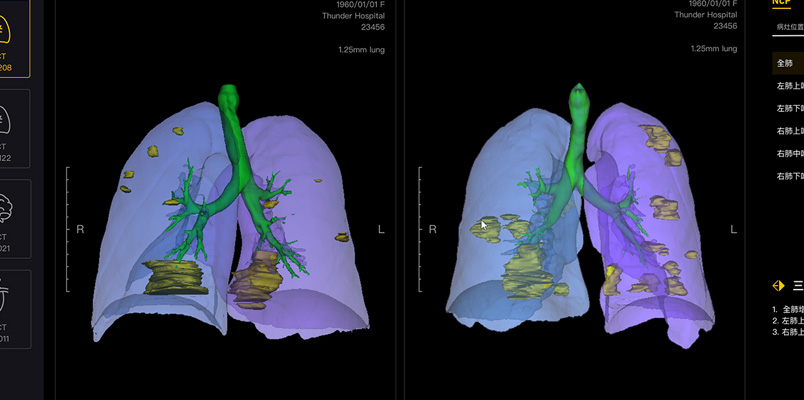

Con las tecnologías de Huawei Technologies, que también incluyen visión por computadora y el análisis de imágenes médicas, los servicios basados en Cloud permiten enviar de manera automática, rápida y correcta los resultados de cuantificación de tomografías a los médicos, aliviando la escasez de médicos que puedan diagnosticar con precisión el COVID-19.

Los estudios de casos sospechosos pueden realizarse en el hospital equipado mediante una tomografía de los pulmones, cuyo resultado ayudará a los médicos a obtener un diagnóstico rápidos menos de un minuto.